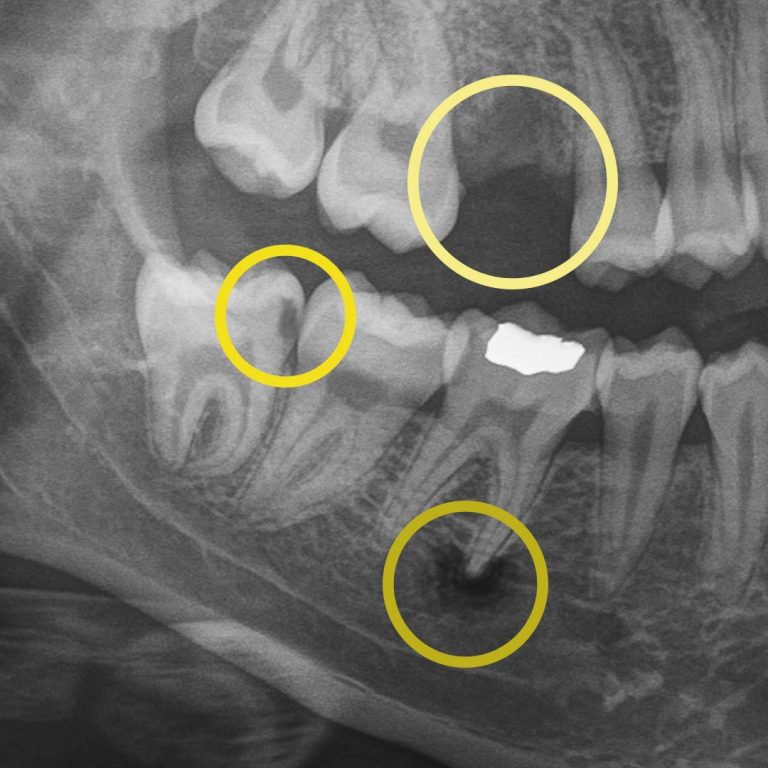

Digital X-rays allow us to look beyond what’s visible. They help us detect:

• cavities between teeth.

• early decay hiding under fillings or crowns.

• bone changes related to gum disease.

• infections at the root of a tooth.

• subtle cracks.

For example, during a routine digital X-ray, we may notice a small shadow between two teeth. To the naked eye, everything can look healthy, but that faint shadow often tells us the enamel in that area is starting to weaken. This is considered early-stage tooth decay, sometimes called early “caries.”

At your next X-ray visit, we’ll compare images to see whether that spot has stabilized or improved. If the area worsens and the enamel breaks down further, a small dental filling may be necessary to prevent deeper decay damaging the tooth structure. If the decay continues unchecked and reaches the inner portion of the tooth where the nerve lives, treatment becomes more complex, often requiring root canal therapy, which can be time-consuming, uncomfortable, and costly.

While catching early tooth decay is one of the most common reasons we rely on digital X-rays, it’s far from the only one. Dental imaging also helps us monitor bone levels to detect gum disease before it leads to tooth loss, identify disease that can’t be seen during an exam, and track hard and soft tissue changes caused by grinding, acid wear, or dietary habits. A complete set of digital X-rays is necessary every few years to ensure the health of all your teeth. This allows you to keep your natural teeth longer.